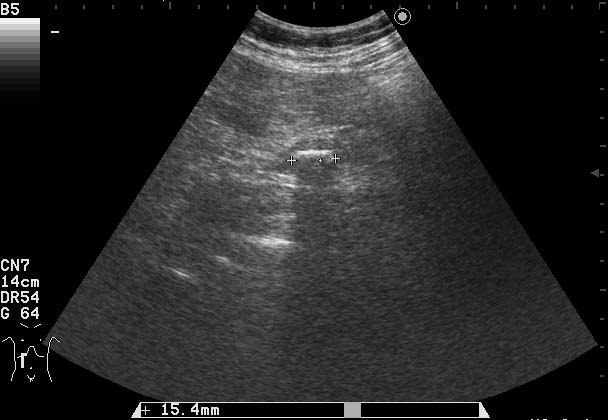

Женщина 70-ти лет с бессимптомной желтухой.

Сонограммы холедоха:

На верхнем снимке можно предположить внутрипросветную опухоль в холедохе.

В сущности, ответ правильный уже был - это опухоль холедоха с инкрустацией ее ткани.

Благодаря такой необычной презентации опухоль была ошибочно принята за камень холедоха.

Спасибо!Очень интересный случай,смотрю уже который раз.Можно ошибиться,но "камень"обволочен мягкотканной структурой-гипоэхогеной,раздвигая стенки коледоха,типа "веретено".Так,что коллега права-опухоль